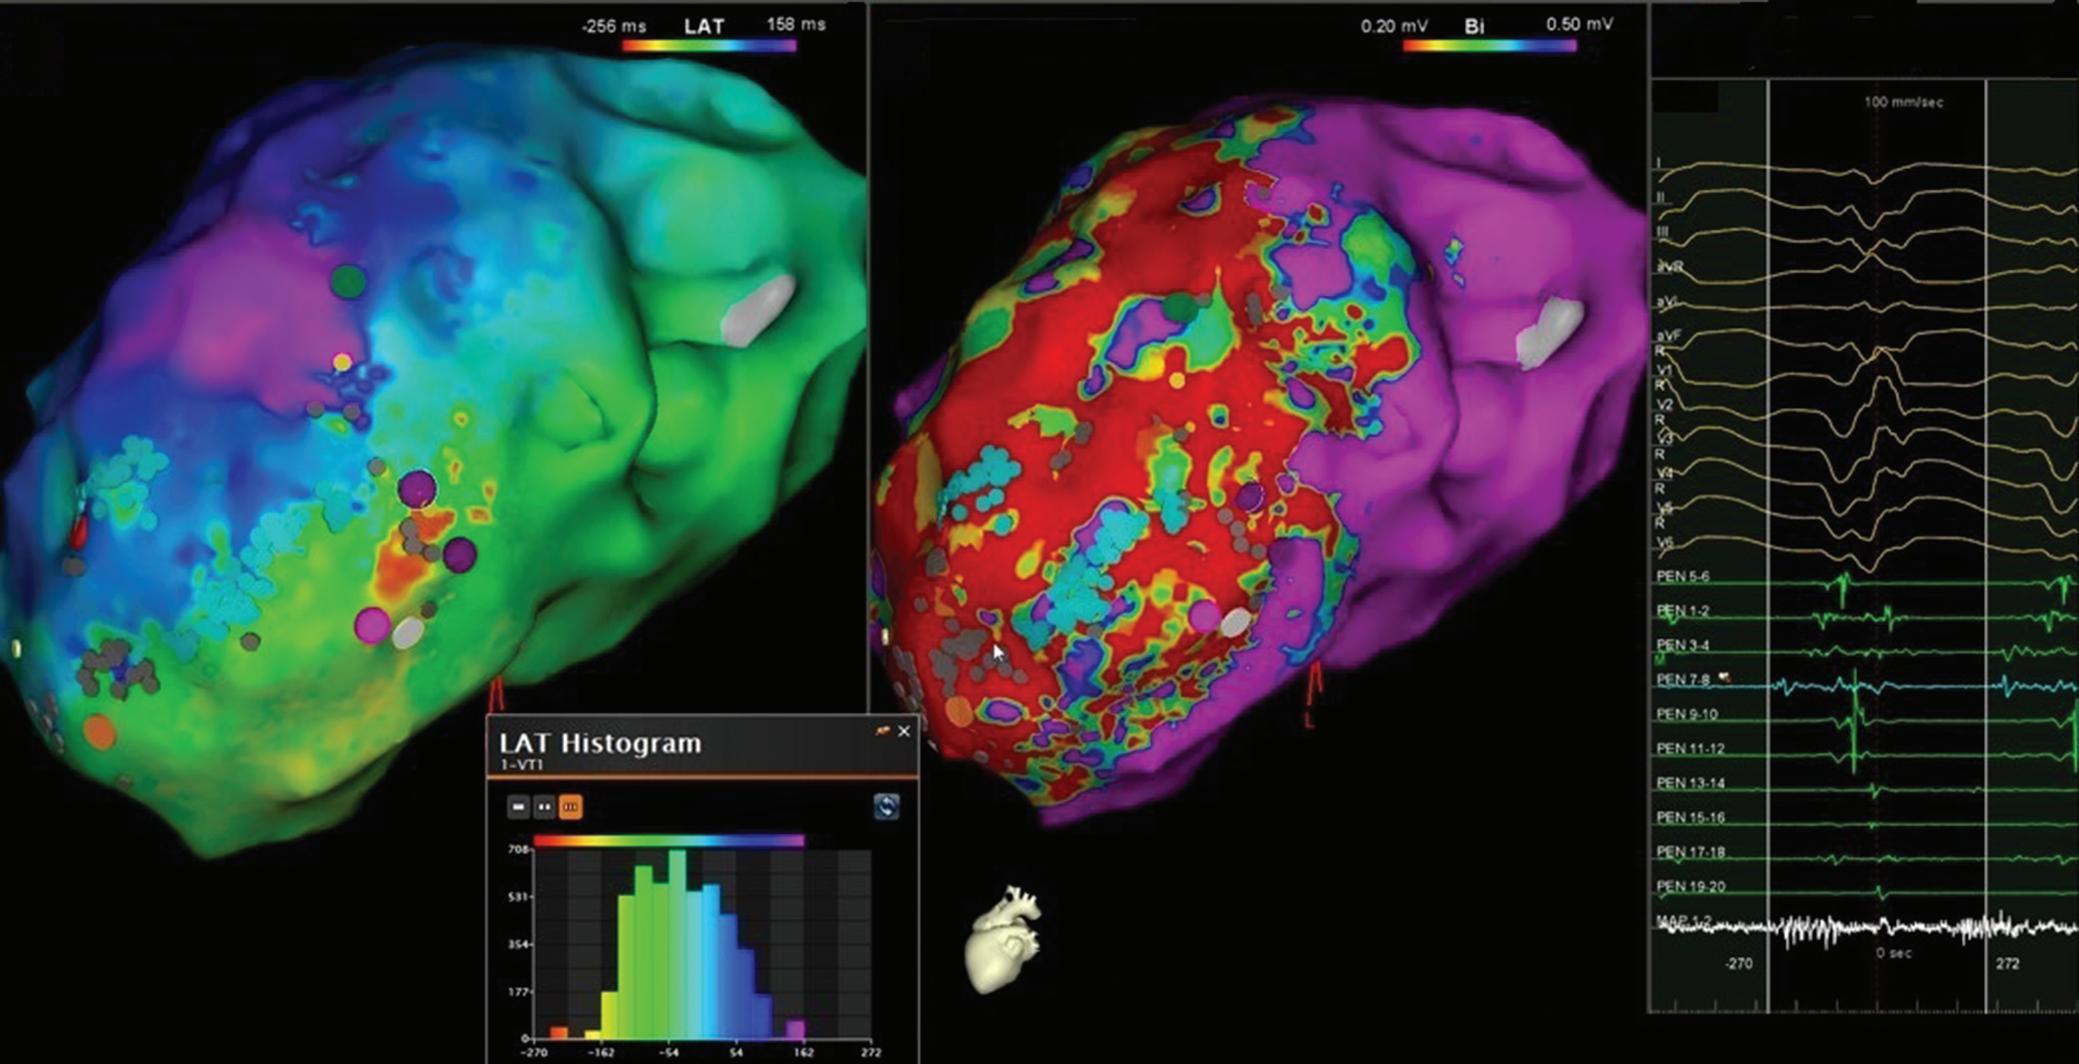

Figure 6: Ventricular Ablation Lesion Assessment

Preprocedural LGE-MRI (1 day before VT ablation)

Ablation points

Post-ablation LGE-MRI (3 months after VT ablation)

Left: 3D reconstruction of the left ventricle with LGE-based colour-coding based on thresholds for dense scar (red, >60% maximum of signal intensity) and border zone (yellow, 40–60% of maximum signal intensity), mapped using ADAS 3D. Shown are the layers at 30% of the transmurality (from endocardial to epicardial). For the post-ablation LGE-MRI (lower panel), an additional 3D reconstruction of the manually defined dark core in red (black arrow) is depicted. Blue lines indicate the plane of the short-axis slices on the right. The ablation points (TactiCath, Abbott Medical) are visualised using a 3D mapping system (EnSite Precision, Abbott Medical). Middle: Overlay of the T1-weighted short-axis slices with the colour-coding described above. The central hypoenhancement dark core of the ablation lesion is manually delineated (red border) to avoid misinterpretation as healthy tissue. Right: T1-weighted short-axis LGE-MRI slices without colour-coding. LGE = late gadolinium enhancement; VT = ventricular tachycardia.

Figure 7: Assessing Elimination of Arrhythmogenic Fibrotic Substrate by Late Gadolinium Enhancement-MRI

Against this background, we have recently analysed the potential role of LGE-MRI to assess the long-term effect of VT ablation in terms of arrhythmogenic substrate elimination (unpublished data). Three to 6 months following the procedure, effective ablation was reflected by pronounced reduction of LGE-MRI-detected border zone scar volume and extent of slow conduction channels compared to the preprocedural LGEMRI (Figure 7). In patients undergoing repeat ablation procedures, this arrhythmogenic substrate elimination as determined by LGE-MRI correlated well with EAM. Thus, LGE-MRI-based lesion assessment may be of potential value to evaluate the efficacy of ventricular substrate ablation and to predict VT recurrences and clinical outcome. However, as mentioned above, clinical validation is warranted.

Left panel: LGE map of the left ventricle prior to substrate-based ventricular tachycardia ablation. LGE depicts an antero-apical scar. A 3D-analysis using the ADAS 3D software predicts a slow-conduction channel (black line) extending over 30 % of the transmurality that was confirmed by invasive electroanatomical mapping. Right panel: LGE map of the left ventricle 3 months post-ventricular tachycardia ablation. LGE indicates complete scar homogenisation and ‘dechannelling’ with ablation lesions covering the full substrate. Percentages indicate distinct layers of the transmurality from endocardial (0%) to epicardial (100%). LGE = late gadolinium enhancement.